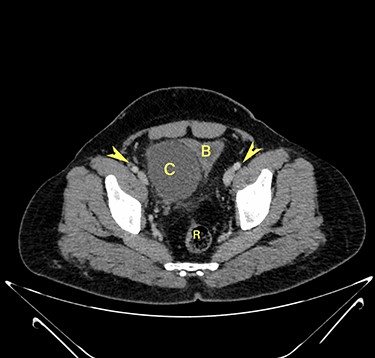

Computerized tomography showed a solitary well defined intraperitoneal cyst consisting of fluid showing low attenuation. The wall of the cyst was 1 cm thick, with no contrast enhancement. It was situated in the pelvis compressing the urinary bladder. It had no communication with either the bowel or the urinary bladder. The pancreas was normal, as also the rest of the abdominal organs. There was no ascites (Figs. 1–5). The diagnosis was a large intraperitoneal infected cyst.

Transverse section image of a contrast-enhanced CT scan of the abdomen at the level 4–4 (Fig. 1), showing a solitary cyst (C) with a non-enhancing wall separate from the urinary bladder (B). Iliac vessels are labelled with arrowheads.